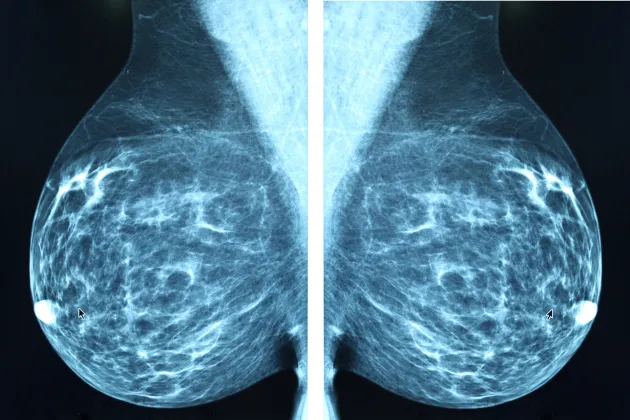

There are many different cancer research initiatives at Lund University. Our research is dedicated to improving the diagnoses, prognoses, treatment and care related to cancer. The most common cancers in Sweden are breast, prostate, and colorectal cancer.

- using imaging and radiotherapy to improve available tools in basic research, treatment and diagnostics

AI model from Lund University indicates four out of ten breast cancer patients could avoid axillary surgery